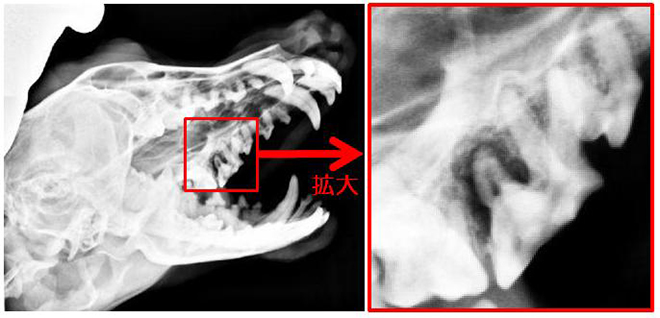

下写真は、ダックスフントで奥歯(臼歯)に問題を起こしてしまった子です。

奥歯が斜めに割れてしまった為に、感染を起こし

歯の根元の骨が溶けてしまい、レントゲンで黒く映っています。

(通常は白く映ります)